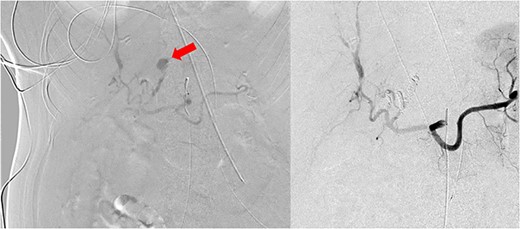

On arrival, the patient was emergently taken to the IR suite for diagnostic angiography and embolization. Angiography identified active extravasation of three separate branches of the left hepatic artery from pseudoaneurysms (Fig. 2). These were embolized. Along the right hepatic arterial system, there was small aneurysmal dilation but no bleeding. Upon completion of her angiogram, she was transferred back to the ICU in critical condition. There was an initial significant improvement in her hemodynamics and stabilization of her hemoglobin. On post-procedure Day 1, the patient again had worsening hemodynamics with a drop in her hemoglobin. A repeat angiogram was performed by IR, but no active bleeding was identified. The hemoglobin again stabilized. Unfortunately, the patient’s clinical picture continued to deteriorate with development of liver failure, kidney failure and worsening respiratory failure despite maximal medical efforts. The family of the patient ultimately decided to pursue comfort focused measures instead of aggressive life sustaining measures and the patient expired on hospital Day 2.

Conventional angiographic images. Left HAP identified on hepatic artery angiogram (left). Following angioembolization, there is no further evidence of bleeding from the liver via celiac artery angiography (right). Red arrow is identifying left HAP.